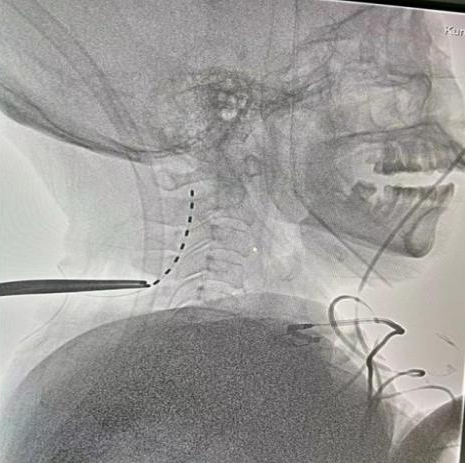

在王文华主任的指导下陈龙主任医师和陆维主治医师成功对该患者开展了脊髓神经电刺激植入术。

图片

▲ST-SCS术后CT:电极位置良好

术后复查CT电极位置良好,1天后开始刺激,频率70Hz,脉宽120,电压1.5V,循环模式:15min on/15min off,工作时间8am-8pm。定期进行CRS-R评分。